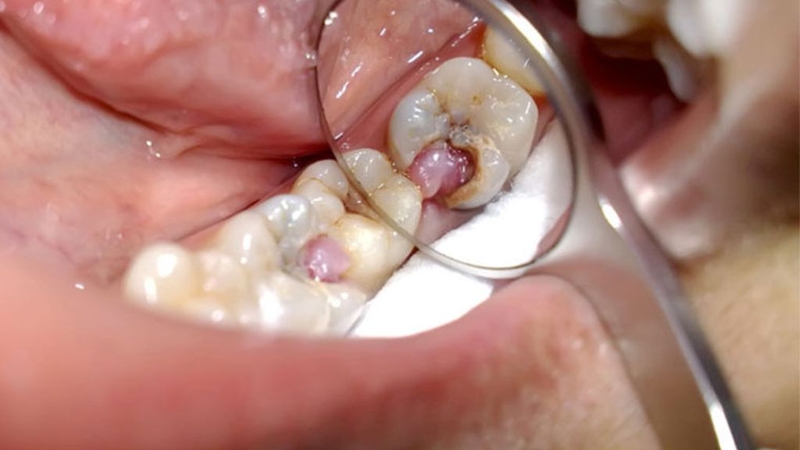

Răng sâu lồi thịt còn có cái tên khác là áp xe răng. Đây là tình trạng răng bị viêm cấp tính nặng. Những ai mắc bệnh sẽ xuất hiện cục thịt lồi ra do niêm mạc bị sưng to, chính phần thịt này làm bệnh nhân luôn đau nhức, thậm chí gây sốt.

Chữa răng sâu lồi thịt bao nhiêu tiền? Bệnh có nguy hiểm? 1

Răng sâu lồi thịt là tình trạng viêm răng nặng